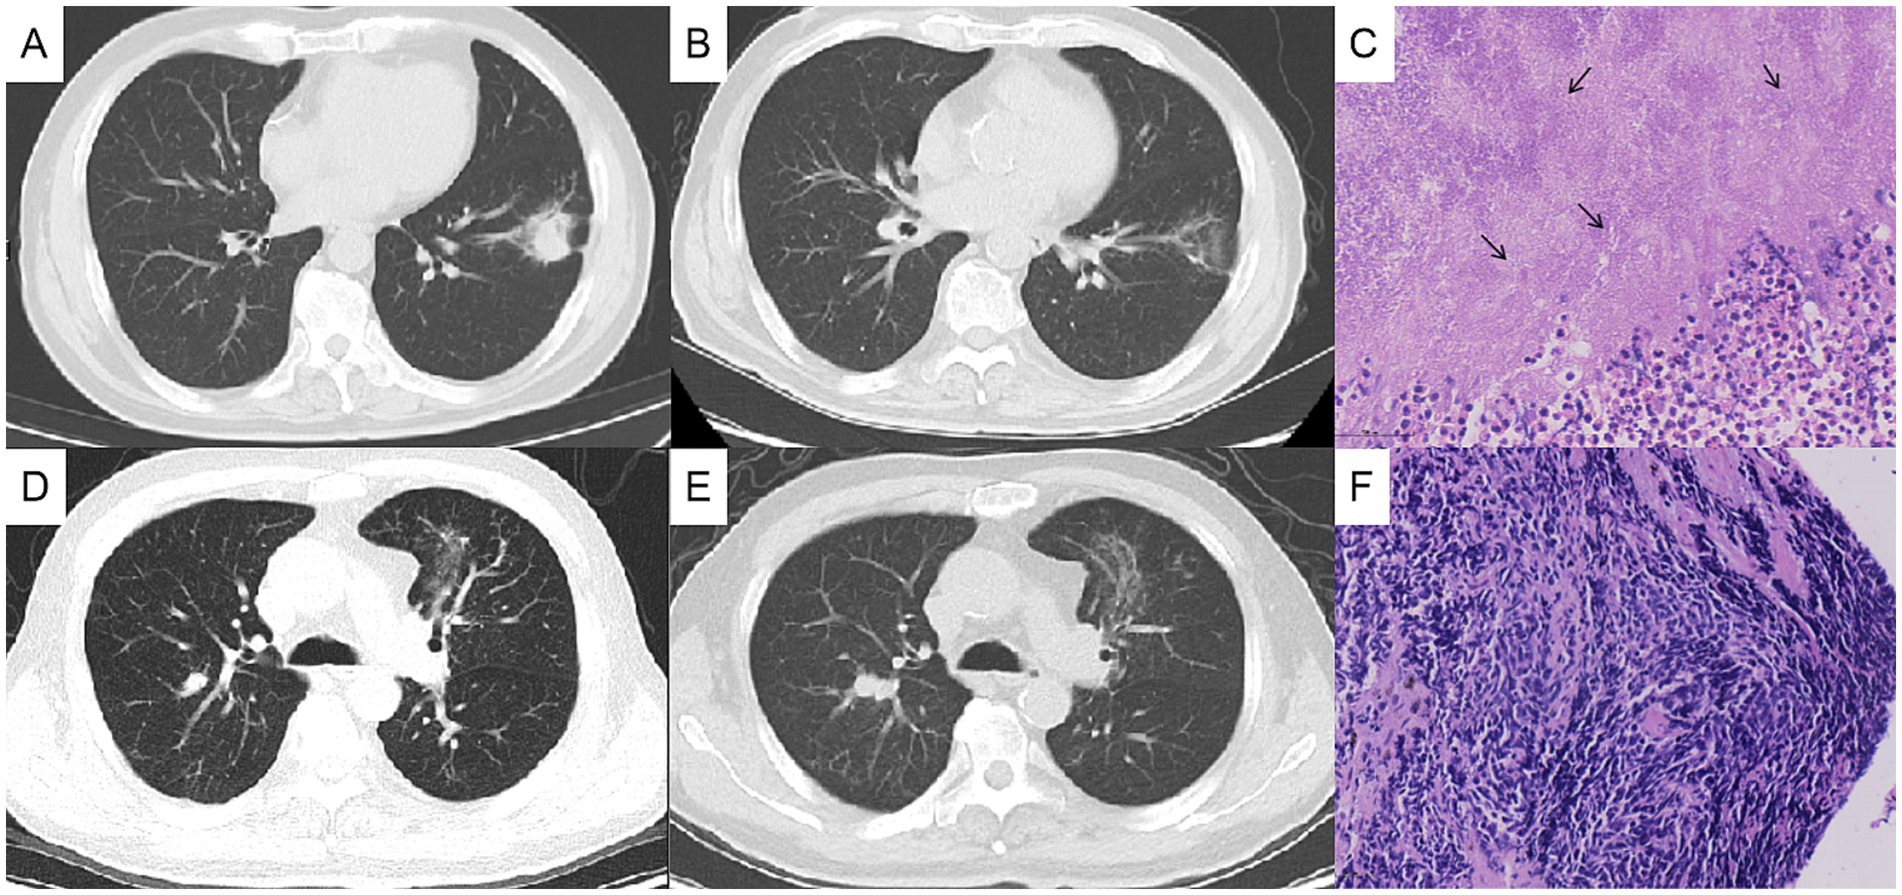

Figure 2

CT scans of lungs in panels A, B, D, and E show variations in tissue density and structure. Histopathology images in panels C and F display tissue samples with cellular details and dark-staining nuclei. Arrows in panel C highlight specific areas of interest.

Figure 2. Chest computed tomography (CT) changes and pathological findings. The left lung mass, measuring approximately 3 cm before treatment (A), showed significant reduction after 1 month of antibacterial therapy (B), and the histopathological analysis of the lung biopsy confirmed actinomycosis (C). The right lung nodule, initially about 1 cm in size before treatment (D), increased to approximately 2 cm after 1 month of oral antibacterial therapy (E), and the bronchoscopic biopsy pathologically confirmed the right pulmonary nodule as lung cancer (F).

After 1 month of antibacterial treatment, the patient’s cough and blood-streaked sputum were significantly reduced. A follow-up chest CT showed a marked reduction in the size of the left lung mass (Figures 2A,B). However, the right lung nodule was larger than before, with a diameter >2 cm (Figures 2D,E). He was readmitted to hospitalization for further evaluation of the right pulmonary nodule.

After admission, the tumor markers were retested, with a serum pro-GRP level of 100.1 ng/mL, significantly elevated compared to 60.5 ng/mL 1 month ago (reference range: 0–70 ng/mL). The patient underwent bronchoscopy under general anesthesia, which showed no abnormalities in bronchial lumen. The endoscopic ultrasonography combined with LungPro navigation-guided transbronchoscopic lung biopsy of the right lung nodule was performed, with the pathological diagnosis of small-cell lung cancer (Figure 2F), which was staged as cT1N0M0. The patient subsequently underwent a thoracoscopic lobectomy of the right upper lung in the thoracic surgery department.